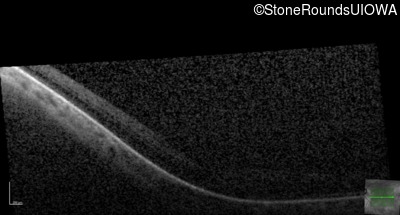

OCT Stack